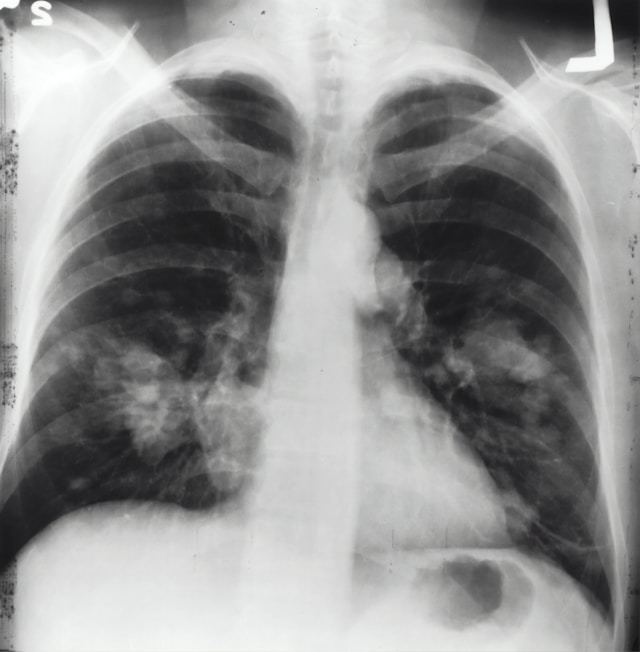

반면 폐렴은 세균, 바이러스 혹은 곰팡이 등의 병원체가 폐 조직에 염증을 일으키는 질환이다. 감기나 기관지염보다 증상이 더 심하고 항생제를 통한 치료가 필요하며, 심할 경우 입원 치료가 필요할 수 있다.

폐렴은 증상이 전형적이지 않아 발견이 늦다. 노인 폐렴은 고열·기침이 뚜렷하지 않은 경우가 많다. 대신 갑작스러운 기력 저하, 식욕 부진, 의식 혼탁, 섬망, 평소보다 숨이 가빠짐 같은 비전형적 증상으로 나타나 진단이 늦어진다.